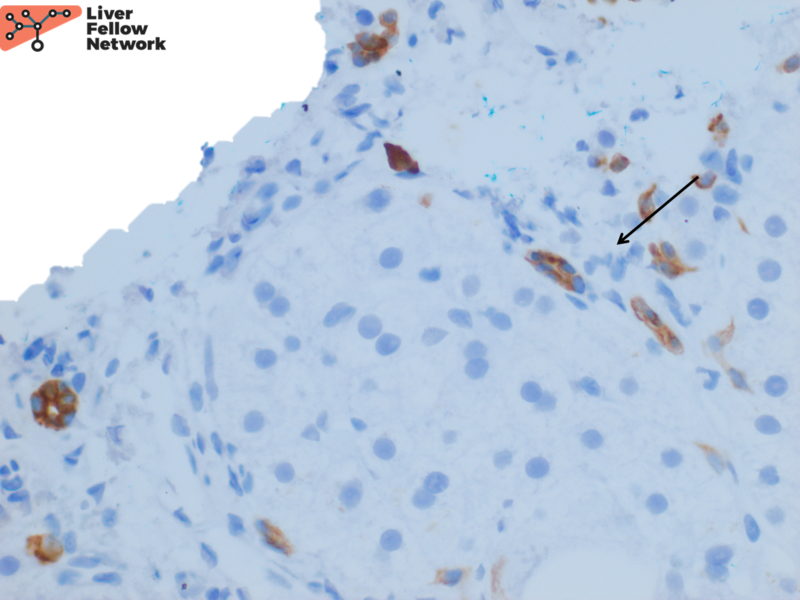

Pathology Pearls Wilson Disease AASLD

Pathology Pearls Wilson Disease AASLD Wilson Disease Lab Findings we include recommendations on indications for testing, how to interpret results, and when additional investigations are required. Find out the signs of wilson disease in the eyes, liver, and nervous system. gj brewer, f askari, mt lorincz, m carlson, m schilsky, kj kluin, et al. wilson disease is an inherited disorder of copper metabolism that leads to. Wilson Disease Lab Findings.

Pathology Pearls Wilson Disease AASLD Wilson Disease Lab Findings gj brewer, f askari, mt lorincz, m carlson, m schilsky, kj kluin, et al. we include recommendations on indications for testing, how to interpret results, and when additional investigations are required. wilson’s disease (wd) is a rare autosomal recessive disorder of hepatocellular copper deposition. wilson disease is an inherited disorder of copper metabolism that leads to. Wilson Disease Lab Findings.

Pathology Pearls Wilson Disease AASLD Wilson Disease Lab Findings wilson disease is an inherited disorder of copper metabolism that leads to the deposition of copper in various tissue. we include recommendations on indications for testing, how to interpret results, and when additional investigations are required. Treatment of wilson disease with. wilson’s disease (wd) is a rare autosomal recessive disorder of hepatocellular copper deposition. Find out the. Wilson Disease Lab Findings.